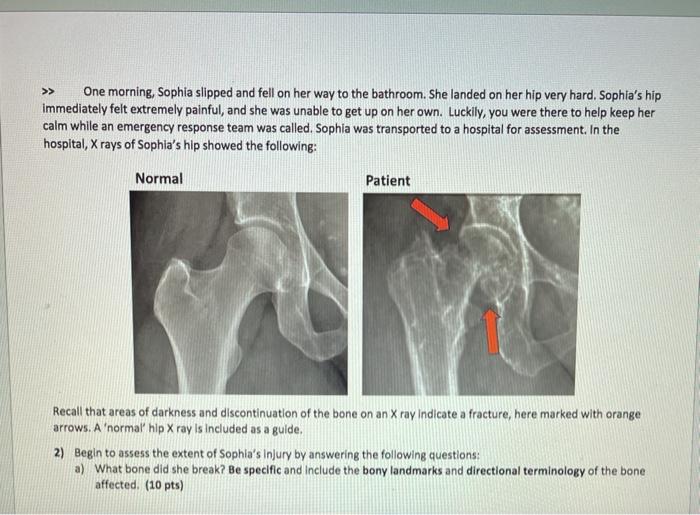

Solved Case Description Sophla Johnson Is 72 Years Old And Chegg Com